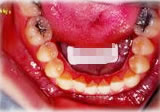

開咬症例

初診時年齢○○歳。前歯部での咬合不全を主訴に来院。

骨格性開咬と診断し、外科的処置を併用して治療。

矯正治療は上下顎歯列を拡大しスペースを作成、非抜歯にて行った。

上顎 上顎 上顎

下顎 下顎 下顎